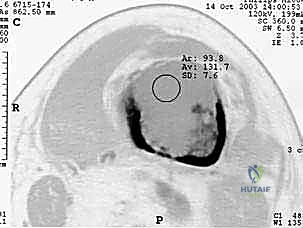

- التصوير بالرنين المغناطيسي (MRI): هو المعيار الذهبي لتقييم امتداد الورم داخل نقي العظم (النخاع) وإلى الأنسجة الرخوة المحيطة. الرنين المغناطيسي يوضح بدقة ما إذا كان الورم يقترب من المفاصل أو الأوعية الدموية.

- التصوير المقطعي المحوسب (CT Scan): يقدم تفاصيل ثلاثية الأبعاد لا مثيل لها لجودة القشرة العظمية المتبقية. يساعد الجراح في التخطيط لحجم المسامير أو الصفائح المطلوبة، وتقييم مدى تدمير العظم.